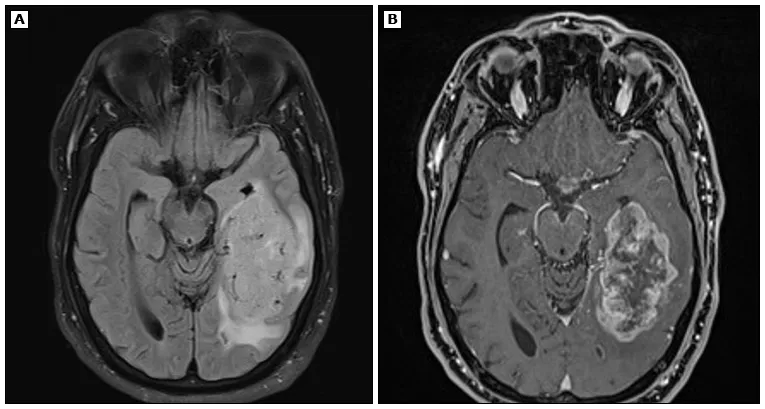

一例53岁男性患者,因持续数周的头痛及找词困难就诊,行头颅MRI检查。FLAIR(图A)及增强后T1加权像(图B)显示左侧颞叶可见一巨大T2高信号肿块,伴不均匀强化及中心坏死。经病理学检查证实为WHO 4级胶质母细胞瘤。